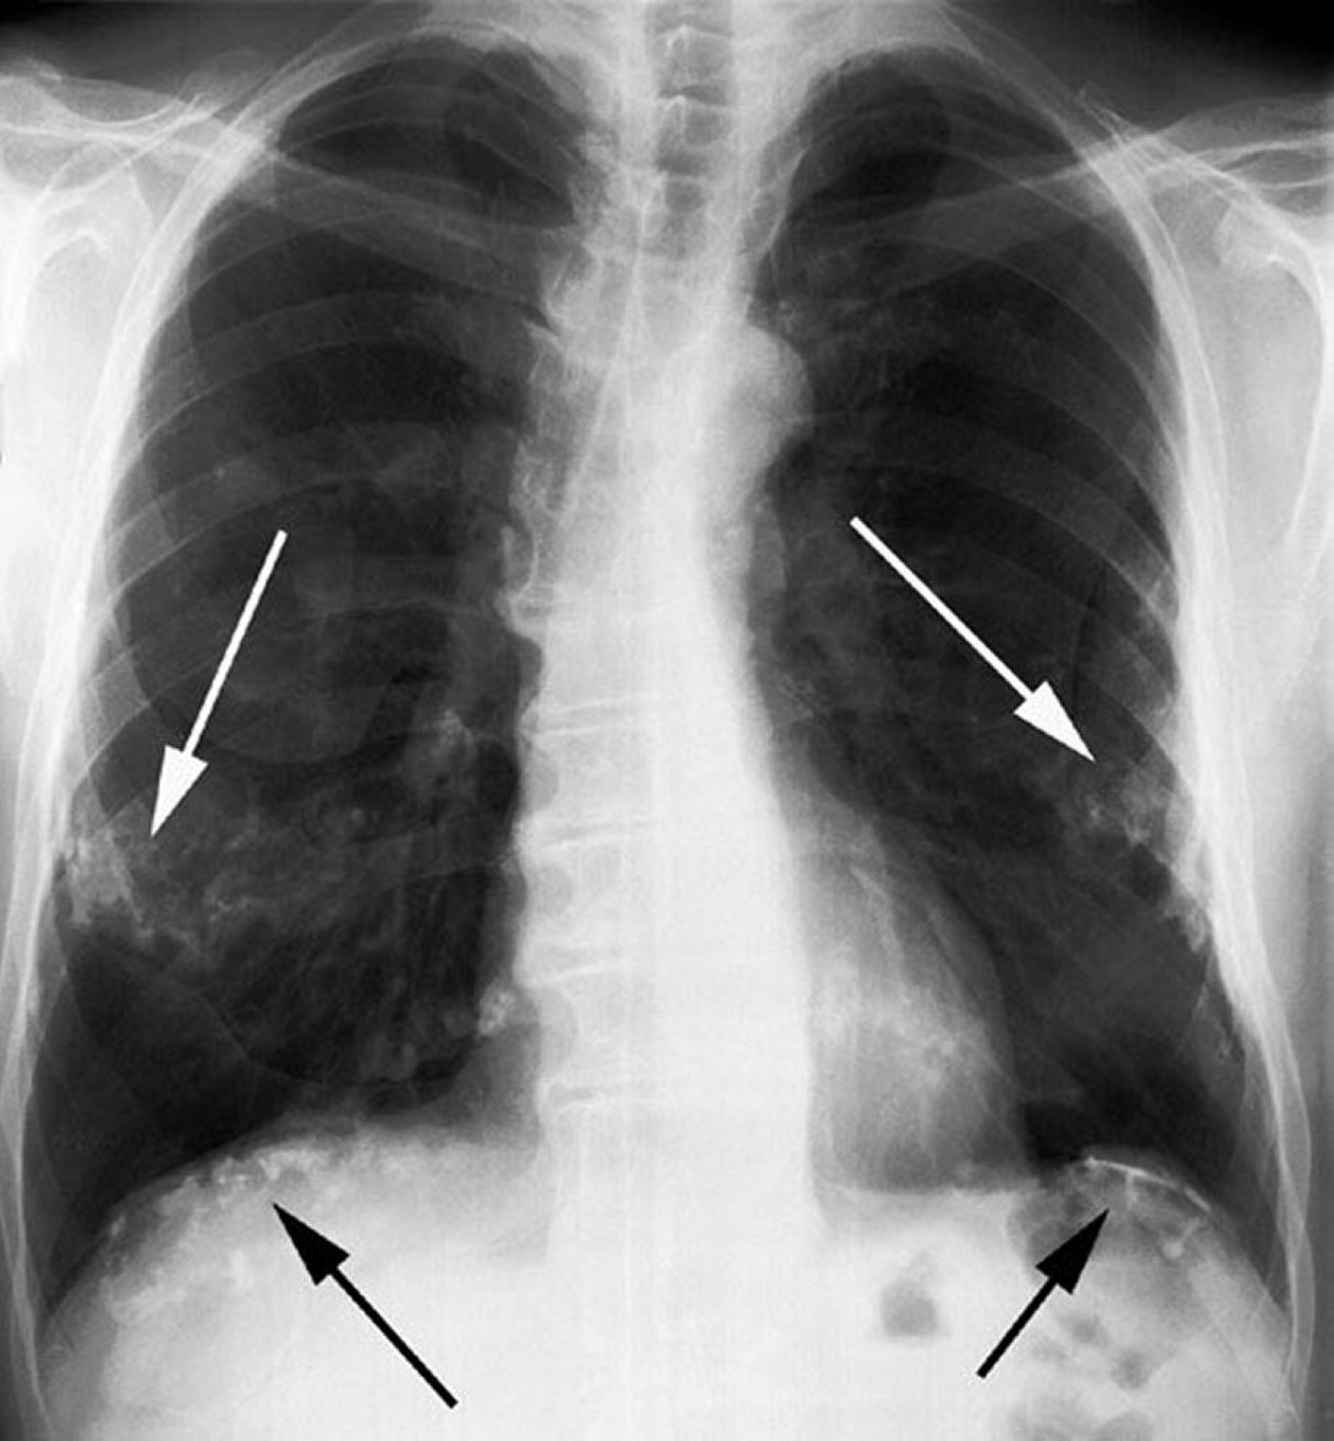

Quais são os achados radiológicos típicos da asbestose na radiografia de tórax?

• Opacidades irregulares ou reticulares, predominando nas bases pulmonares

• Placas pleurais associadas (calcificadas ou não)

• Espessamento pleural difuso, a doença relacionada ao asbesto mais prevalente

• Atelectasia redonda com distorção vascular em cauda de cometa

A asbestose tende a ser proeminente nos lobos inferiores e áreas subpleurais. Verdadeiro ou falso?

Verdadeiro.

A asbestose afeta principalmente os lobos inferiores e áreas subpleurais, onde as fibras de amianto se depositam e causam fibrose intersticial difusa.